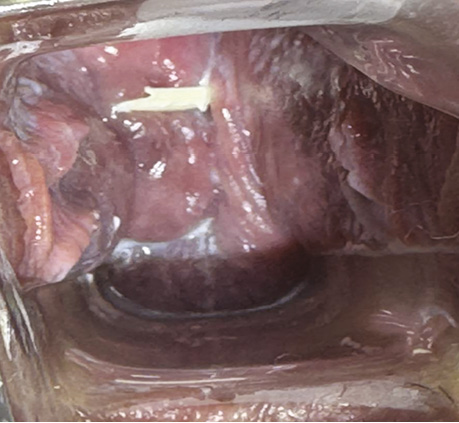

Проведено вагінальне дослідження. Цитологічний висновок від 13.07.2023 р. № 4735/23 — тип II. Запальний тип мазка (рис. 9).

Рис. 9. Шийково-матковий анастомоз після ПВТ